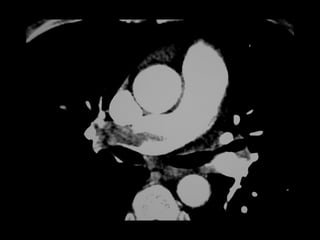

 Masculino, 74 anos

 Dispneia súbita há 1 dia

 AP:

 TEP prévio após fratura de fêmur D

 Mobilidade reduzida

 Varizes de MMII



EF: FC 110 bpm, SpO2 78% a.a.

Edema unilateral MI D